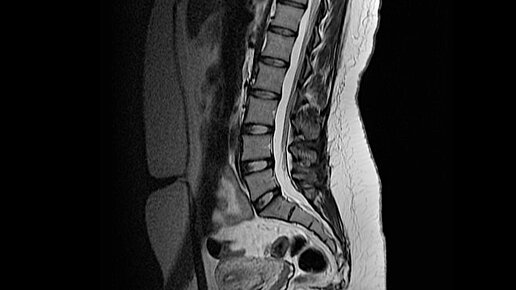

Что лучше подходит для диагностики заболеваний позвоночника КТ или МРТ?

Метод исследования и выявления проблем, как правило, назначает врач, исходя из предварительного диагноза. Основным диагностическим методом на 2022 год является лучевая терапия — КТ (компьютерная томография) и МРТ ( магнитно - резонансная томография ). Если у вас возникли проблемы с позвоночником, то вам назначат один из этих методов диагностики, возможно даже оба. Давайте разберемся, чем эти методы отличаются друг от друга и какой из них более эффективный. Особенности и технология реализации КТ...